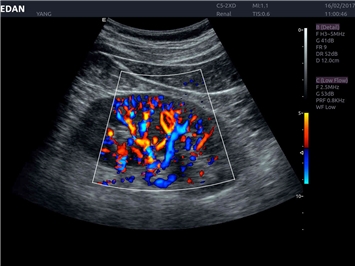

EDAN Acclarix LX4 представляет собой инновационную ультразвуковую систему, построенную на усовершенствованной платформе Acclarix. Сочетание высокого качества визуализации с интеллектуальным рабочим процессом делает эту систему оптимальным выбором для клиник, ценящих эффективность и экономичность.

Передовые технологии визуализации:

Инновационные функции обработки изображений:

• Запатентованная технология адаптивной визуализации тканей

• Функция eSRI для подавления зернистости изображения

• 3D/4D-визуализация с автоматическим редактированием объема (eFace)

• Панорамная визуализация

• Тканевая допплеровская визуализация (TDI)

• Специализированная технология визуализации иглы

Области применения:

Система Acclarix LX4 оптимально подходит для:

• Общей визуализации

• Акушерства и гинекологии

• Кардиологических исследований

• Сосудистой диагностики

• Педиатрии

• Исследования малых органов